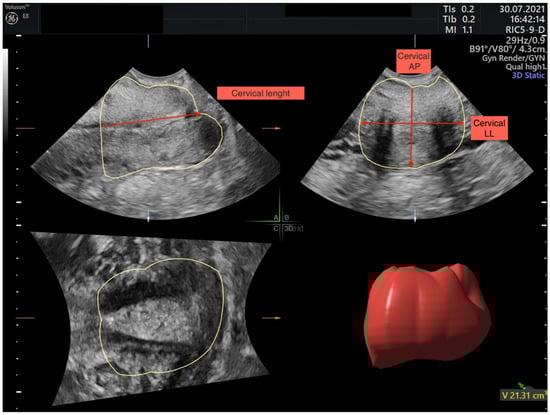

- In the middle part of the cervix, measurements in the transverse plane will include anteroposterior (AP) and transverse diameters (LL) (Figure 2).

Figure 2. Multiplanar planes after image acquisition. In plane (A) sagittal cervix image, in plane (B) transverse cervix image, and in plane (C) coronal cervix image are shown. In sagittal plane cervical example for cervical length measurement, in transverse plane example for cervical anteroposterior (AP) and latero-lateral (LL) measurements are made. - Cervical volume will be calculated with two methods:

- With Virtual Organ Computer-Aided Analysis software (VOCAL) (Figure 2).

The cervix is visualised in three planes, sagittal (A), transverse (B), and coronal (C), and measured through uterine cervix VOCAL (3D) volume measurements and cervical length (CL), antero-posterior (AP), and latero-lateral (LL) measurements.